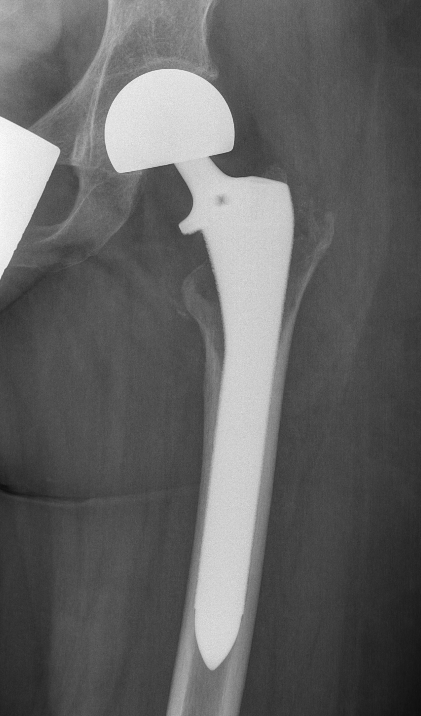

Wide resection and Allograft / Prosthesis Reconstruction

Indications

- extensive soft tissue tumour

- extensive cortical destruction

- impossible joint salvage

- multiple recurrence / failure bone cement

May allow surgical downstaging

- surgically unsalvageable / surgical treatment high morbidity

- arthrodesis or arthroplasty in young patients

Results

- prospective study of 20 patients with GCT

- pre-operative treatment with Denosumab

- pain relief in the first month

- improved radiological response with improved subchondral and cortical bone

- increased intra-lesional resection and joint preservation

- no effect on recurrence

Rutkowski et al Ann Surg Oncol 2015

- 222 patients at risk for wide resection treated with Denosumab

- allowed joint preservation in 96% of those thought to require joint replacement

- allowed joint preservation in 86% of those thought to require wide resection / arthrodesis

- recurrence rate 15%